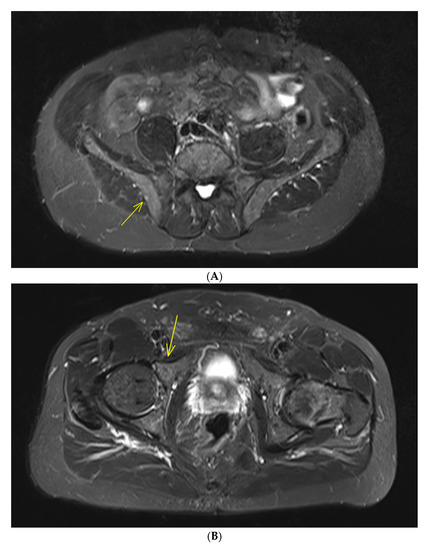

Studies relating to conventional magnetic resonance imaging (MRI) in patients with SMM have also shown presence of more than 1 FL (with size > 5 mm) was predicting of rapid progression to active MM, leading to inclusion of this biomarker as MDE (Figure 1). Indeed, in a large cohort of 149 SMM patients assessed by conventional WBMRI, presence of more than one FL was a strong adverse prognostic factor for progression into symptomatic MM (more than 60% at 2 years) in multivariate analysis, as well as diffuse bone marrow infiltration pattern [12]. These results have been confirmed in a smaller study of 67 SMM patients assessed by spinal MRI [13]. For patients with more than one FL, the 1-year progression to symptomatic MM rate was 44%, the 2-year progression rate was 69% and the 3-year progression rate was 85%, versus 1-, 2- and 3-year progression rates for those with no FL of 8%, 13% and 22%, respectively.

Figure 1.

IgGk smoldering multiple myeloma (SMM) patient with negative whole-body computed tomography. Magnetic resonance imaging of the rachis and pelvis shows two focal bone lesions with increased signal intensity in T2-weighted STIR (short-tau inversion recovery) images. One small lesion (diameter: 5 mm) of the right iliac crest (A) and one bigger lesion (diameter: 14 mm) of the right acetabulum anterior column (B), with corresponding enhancement after Gadolinium injection in T1-weighted images with fat saturation (C,D). No further focal lesion of the rachis was detected in whole-rachis sagittal T1-weighted and T2-weighted STIR sequences (E,F). These two focal bone lesions are considered a myeloma-defining event leading to the recommendation to treat this patient.